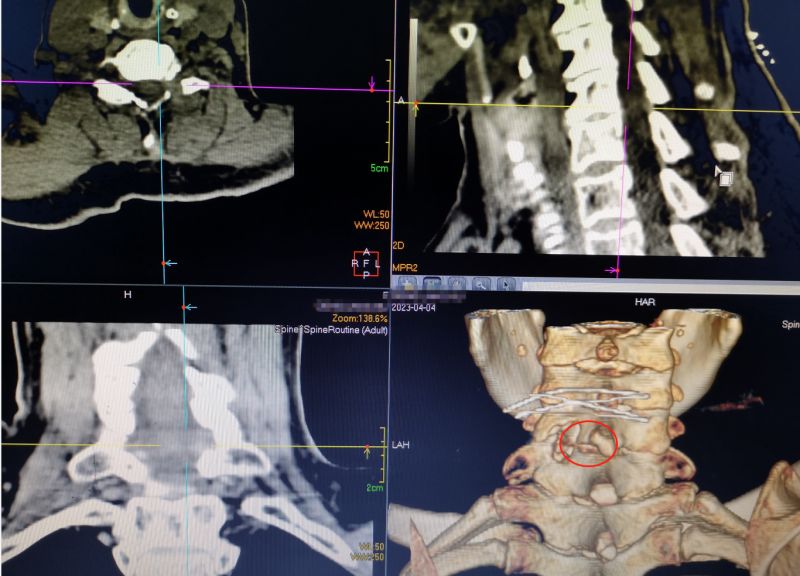

4.术后复查CT见突出的椎间盘已摘除干净,椎板上仅仅打开一个小孔不影响活动,也无需上螺钉固定

此次邓阿姨从湖南道县专程到南溪山医院主要想解决颈椎疾患带来的病痛,脊柱外科主任李亮博士接诊后为她安排了全面检查,她的影像学结果显示第6—第7颈椎间盘突出并刺激压迫左侧神经根,需要进行手术。完善术前准备后,熊宇副主任医师主刀为邓阿姨实施了微创“钥匙孔手术”——颈椎后路脊柱内镜下颈椎管减压髓核摘除射频消融术。手术非常顺利,麻醉清醒后,邓阿姨颈肩部及左上肢的疼痛症状当即消失了,四肢活动正常。第二天,邓阿姨女儿高兴地说:“我妈妈终于睡了个整觉!”